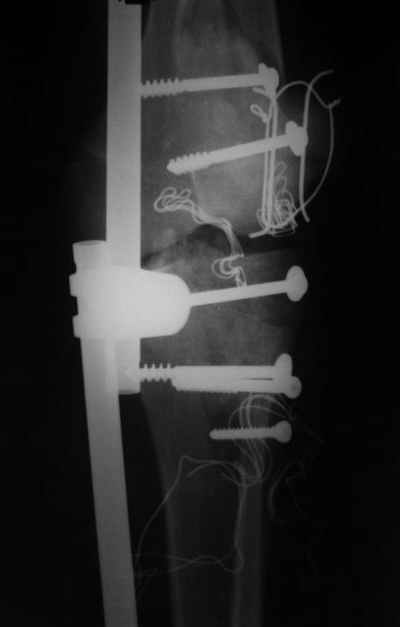

Re: открытый перелом мыщелков бедра, латерального

Вид раны на сегодня...

4 cутки после травмы.

Спасибо за комментарии. Травма тяжелая с проблематичным прогнозом для функции коленного сустава( изначально травма разгибательного аппарата с последующим частичным некрозом собственной связки надколенника и о обнажением рефиксированного фрагмента бугристости большеберцовой кости, дефектом центрального отдела суставной поверхности большеберцовой кости и медиального отдела капсулы сустава).